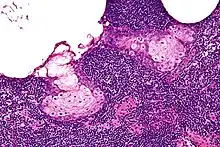

| High magnification micrograph of a sebaceous lymphadenoma. H&E stain. | |

Sebaceous lymphadenoma is a benign tumour of the salivary gland.[1]